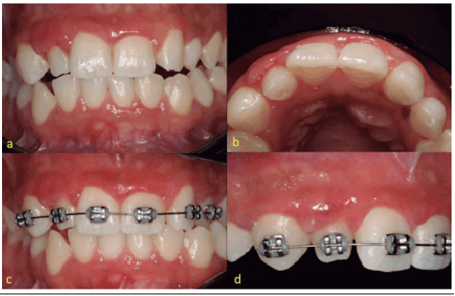

After 18 months of clinical follow-up, although the patient presented mild hyperplasia in the upper lateral incisor, as a result of poor dental position, she presented adequate oral hygiene proven by auxiliary methods such as dental plaque disclosing agent, in addition to periodontal probing (Figure 4a, 4b). There was no recurrence of gingival growth and absence of regions with gingival bleeding after periodontal probing (Figure 4c, 4d). The patient is undergoing medical treatment with no systemic changes due to the change in anticonvulsive drug therapy and an orthodontic treatment plan for realignment and bite descrucing in the upper right quadrant was instituted (Figure 5a, 5b, 5c, 5d).